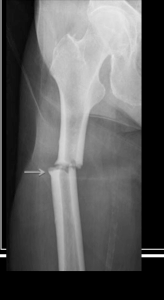

Stress fracture

Due to repetitive use. Also called hairline fracture. Appears like a crack on a x-ray